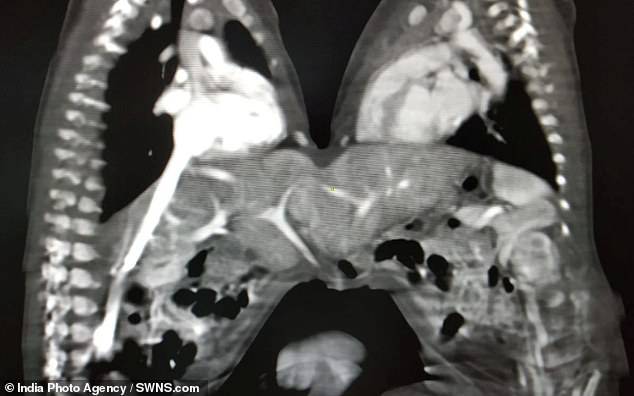

Un team di chirurghi ha operato con successo due gemelline siamesi di 3 giorni unite per lo stomaco. L’operazione si è svolta il 6 dicembre scorso nello Stato dell’Uttar Pradesh, dopo che i medici sono riusciti a convincere i genitori delle neonate della necessità dell’intervento.

L’intervento è durato 5 ore e ha richiesto la partecipazione di

- 5 chirurghi,

- 10 medici

- e 15 infermiere.

Si è trattato di un’operazione particolarmente difficile, non solo per la rarità del caso, ma anche per la loro piccola scorta di sangue.